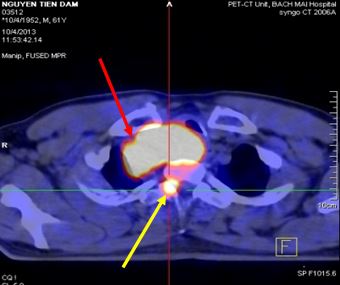

- Hình ảnh PET/CT:

Kết quả PET/CT: Hình ảnh khối u thùy trên phổi phải (mũi tên đỏ) kích thước 5,6x6,9x9,0cm, tăng hấp thu F-18 FDG, max SUV=13,18, chèn ép làm hẹp lòng khí quản, hạch lớn trung thất tăng hấp thu F-18 FDG. Tổn thương đốt sống D2 (mũi tên vàng) tăng hấp thu F-18 FDG, max SUV=8,85. |